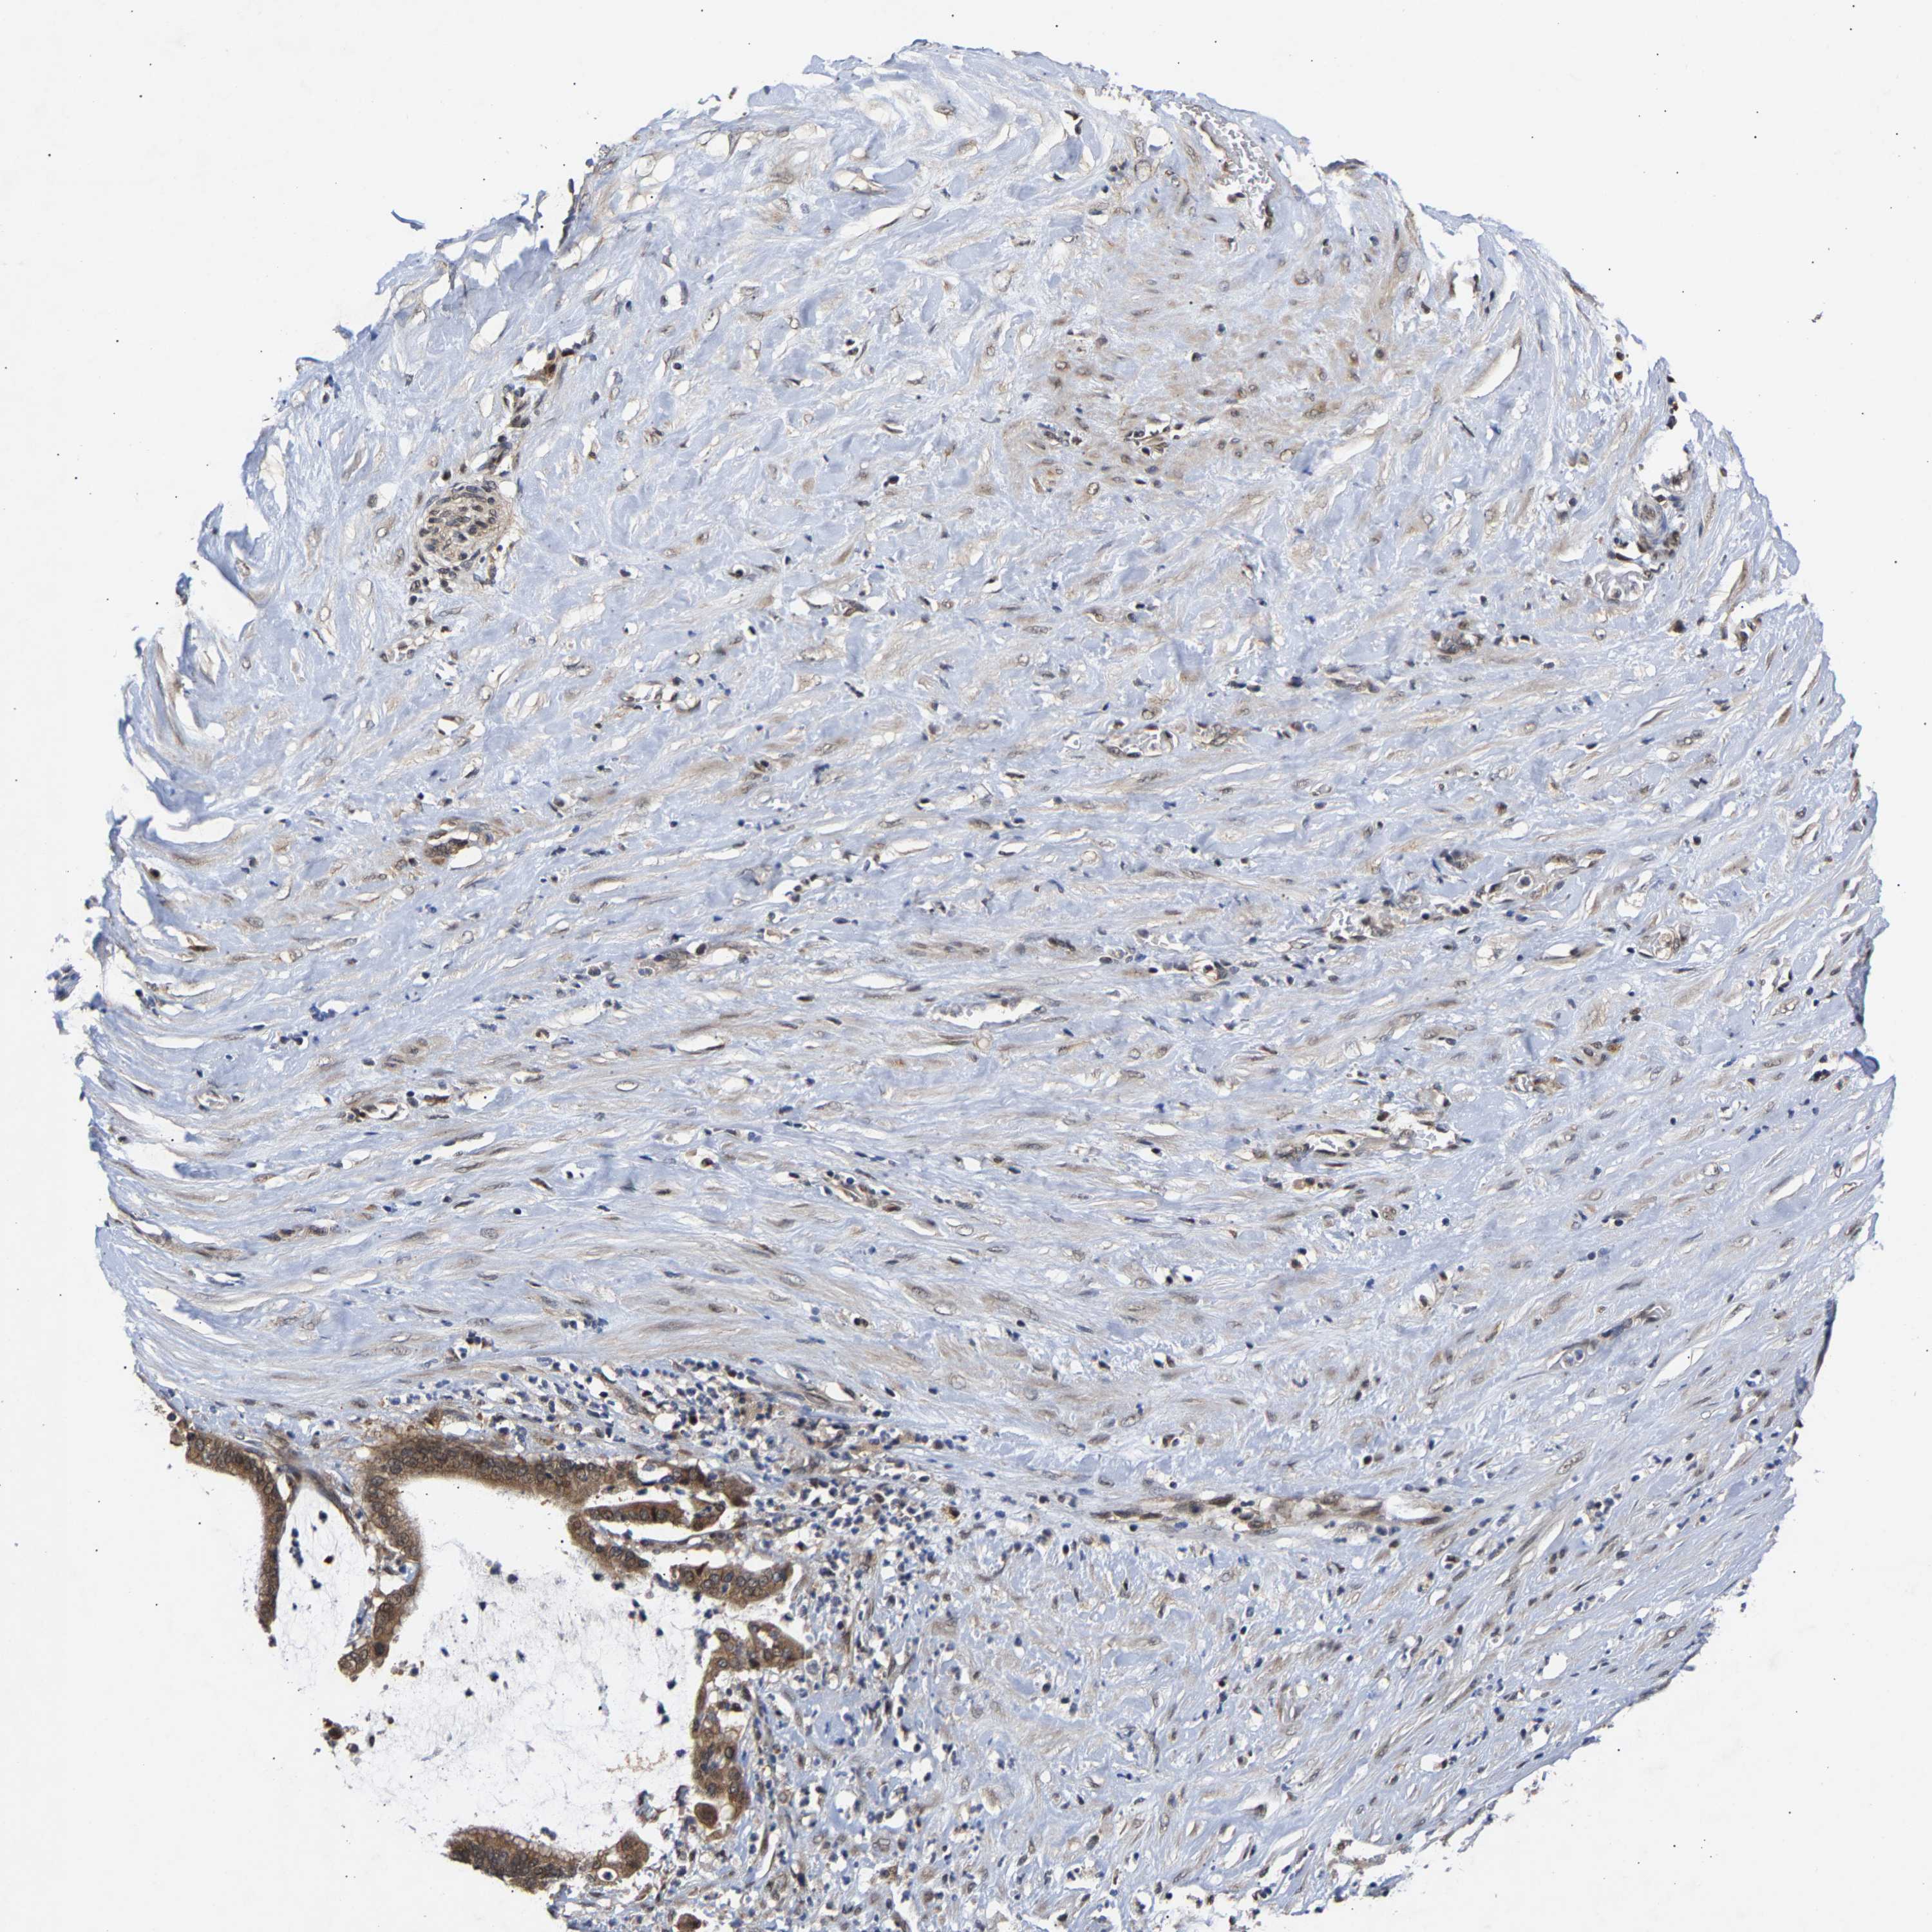

PANCREATIC CANCER - Protein expressioni

A mouse-over function shows sample information and annotation data. Click on an image to view it in a full screen mode. Samples can be filtered based on level of antibody staining by selecting one or several of the following categories: high, medium, low and not detected. The assay and annotation is described here.

Note that samples used for immunohistochemistry by the Human Protein Atlas do not correspond to samples in the TCGA dataset.

Antibody stainingi

Antibody staining in the annotated cell types in the current human tissue is reported as not detected, low, medium, or high, based on conventional immunohistochemistry profiling in selected tissues. This score is based on the combination of the staining intensity and fraction of stained cells.

Each image is clickable and will lead to virtual microscopy that enables deeper exploration of all samples and also displays staining intensity scores, fraction scores and subcellular localization as well as patient and tissue information for each sample.

Antibody HPA020430

Antibody CAB020767

Staining

High

Medium

Low

Not detected

Intensity

Strong

Moderate

Weak

Negative

Quantity

>75%

75%-25%

<25%

None

Location

Nuclear

Cytoplasmic/membranous

Cytoplasmic/membranous,nuclear

Adenocarcinoma, NOS